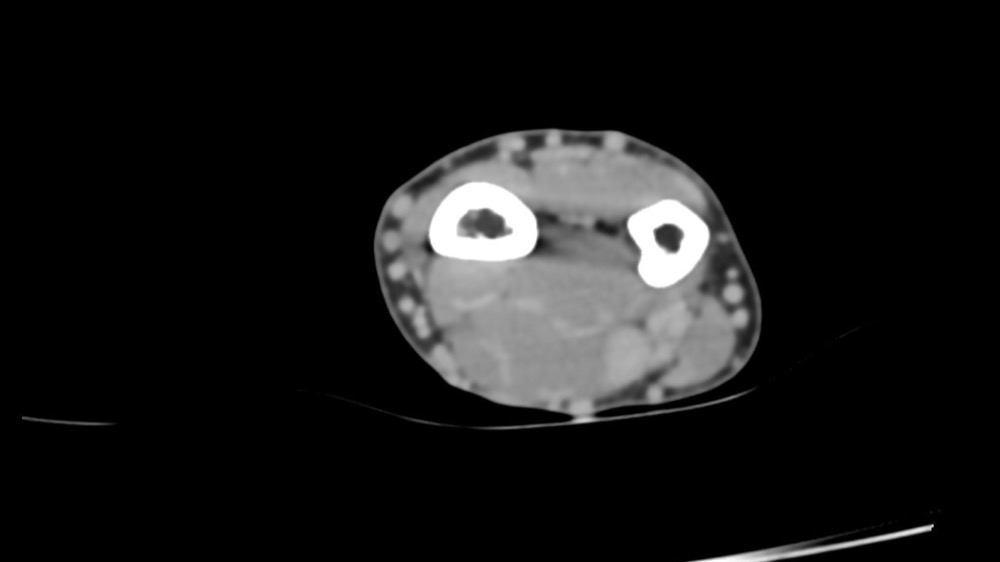

Bone Club

Thomas Leclerc 23/03/2022